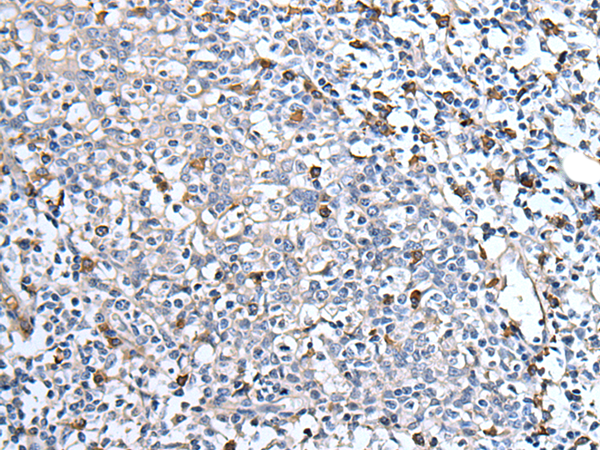

IHC positive control: |

Human tonsil |

IHC Recommend dilution: |

25-100 |